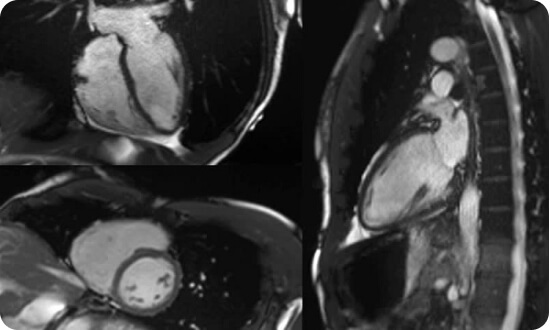

MRI Tim

- Kiểm soát nhịp thở và thở tự do để tăng tương phản giữa các cấu trúc và mạch máu

- Tạo ảnh động cho phép đánh giá van tim với độ phân giải cao

- Đánh giá tình trạng mô với chất lượng cao

- Các chương tình chụp tim gắng sức và thư giãn với độ phân giải cao

- Đánh giá tốt bệnh lý cơ tim, van tim,…

- Đánh giá trước phẫu thuật trong các bệnh tim bẩm sinh